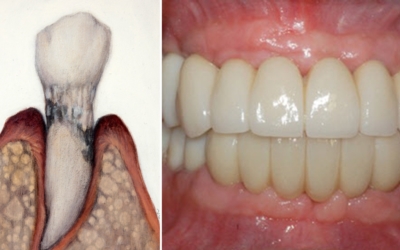

치은염에서 발전된 형태의 잇몸 염증 질환을 말합니다. 치은염이 잇몸 겉에 염증이 생긴 정도라면 치주염은 잇몸 겉에서 잇몸 뼈 주변까지 염증이 진행된 형태입니다. 따라서, 치은염보다 치료기간도 길어질 수밖에 없고 회복도 더딘 편입니다. 치주염은 치은염에서 발전된 형태이기 때문에 초기에는 양치질을 할 때 피가 나는 등의 치은염 증상을 겪게 돼요. 이후 치주염으로 발전한 초기에는 잇몸이 붓고 들뜬 느낌이 들며 붉어지고 건드렸을 때 출혈이 발생하게 돼요. 중기에는 잇몸이 내려가며 이 사이가 뜨기 시작해 치아가 조금씩 흔들리게 되고 말기에는 잇몸이 심하게 내려가 치아가 많이 흔들리게 돼요.

잇몸에 붓기가 생기고 통증이 발생하는 경우의 대부분은 우리의 치은과 관련이 있어요. 치은이란, 잇몸을 말하고 이곳에 염증이 생기면 이를 치은염이라고 합니다.흔히 치아 관리를 제대로 하지 않아 플라그라는 세균막이 생기며 석회화 된 치석이 잇몸과 치아 사이를 벌어지게 하는데 이 부분에 세균이 침투하고 염증을 발생시키면서 치은염으로 발전하게 돼요.

양치질을 할 때 피가 나고 입 냄새가 심해질 수 있으며 식사를 할 때 불편함을 느끼는 등 잇몸이 붓고 아플때 치은염을 의심해볼 수 있어요. 치은염을 계속 방치하게 될 경우 치아 주위 조직에 까지 염증이 번지는 치주염으로 발전할 수 있으니 잇몸에 이상을 장기간 느끼신다면 치과에 방문해 진단을 받아보셔야 합니다.